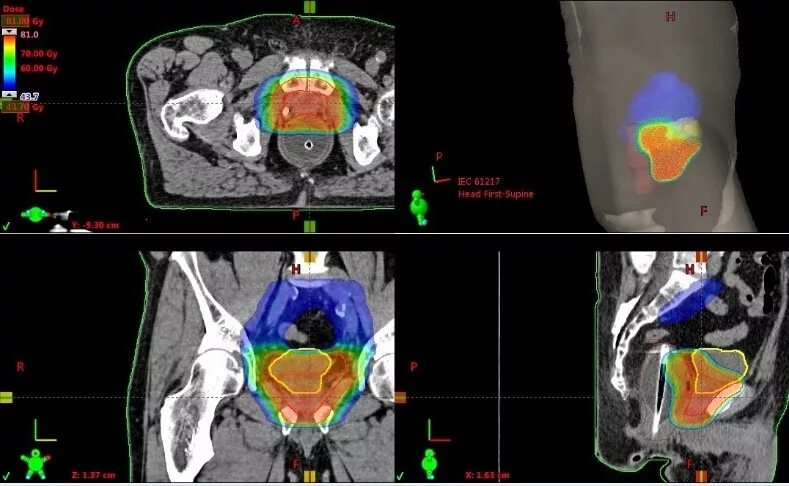

Трехмерная конформная лучевая терапия. трехмерная конформная лучевая терапия (3d-crt). дистанционная лучевая терапия предстательной железы. лучевая терапия при онкологии предстательной железы.

Дистанционная лучевая терапия предстательной железы. 3d конформная лучевая терапия. конформная дистанционная лучевая терапия это. трехмерная конформная лучевая терапия (3d-crt).

Конформная дистанционная лучевая терапия это. дозы лучевой терапии. дистанционные методы лучевой терапии. длительность лучевой терапии.

3д конформная лучевая терапия. конформная дистанционная лучевая терапия это. трехмерная конформная лучевая терапия (3d-crt). дистанционная лучевая терапия предстательной железы.